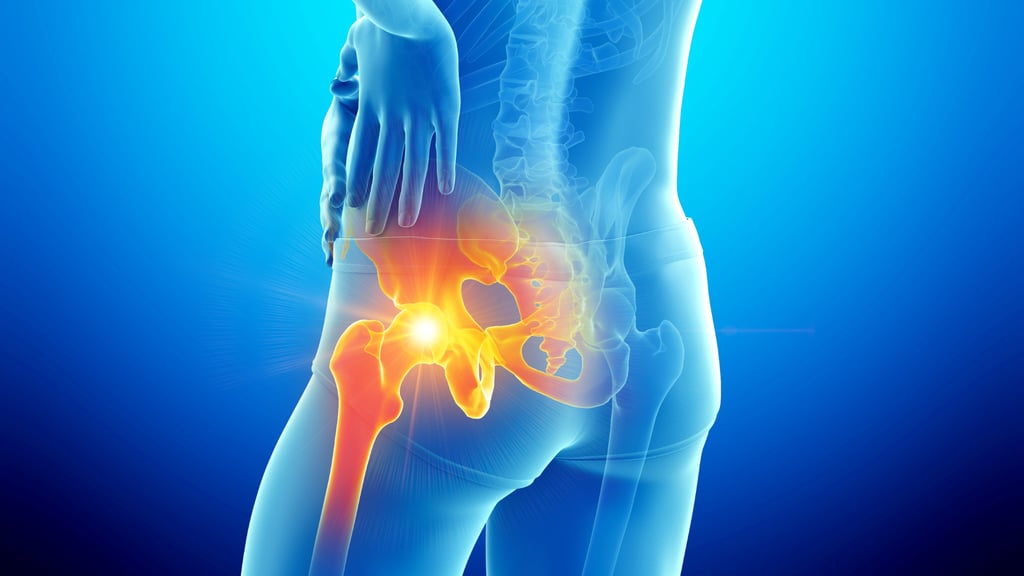

Η οστεοπόρωση είναι μια πάθηση που χαρακτηρίζεται από αδυναμία των οστών, κάνοντάς τα πιο επιρρεπή σε κατάγματα. Είναι πιο συχνή στις γυναίκες μετά την εμμηνόπαυση, αλλά μπορεί να επηρεάσει και τους άντρες. Μέσω σωστής διατροφής, άσκησης και φαρμακευτικής αγωγής, μπορεί να προληφθεί ή να ελεγχθεί. Η πρώιμη διάγνωση είναι κρίσιμη για την αποφυγή σοβαρών καταγμάτων και τη διατήρηση της ποιότητας ζωής.

Οστεοπόρωση